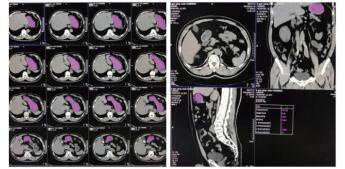

1.3 CT计算胃残余量和超声测定胃窦截面积⑴CT计算胃残余量:使用64排128层4D螺旋CT机(SOMATOM Definition AS型,德国SIEMENS公司)进行腹部CT检查,然后利用VOLUME-Work Flow医学图像软件(德国SIEMENS公司)对CT图像进行分析,即以Freehand方式对胃进行描记,从胃底开始逐层勾画胃壁轮廓形态并进行修正,以及设置CT评估限值,最终通过软件自动计算出胃腔总容积、胃腔气体容积、胃腔非气体容积及胃腔容积高度,其中胃腔非气体容积为患者胃残余量值(见图 1)。

|

| 图 1 CT检测胃容积的方法(左:描计胃轮廓;右:胃残余量计算) Fig 1 The capacity of stomach measured by CT (Left, the tracing of gastric outline; Right, the calculation of gastric residual volume) |